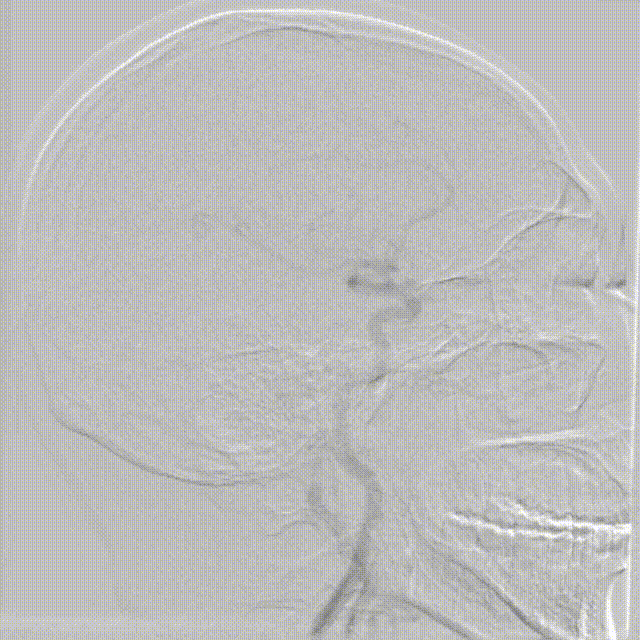

影像信息